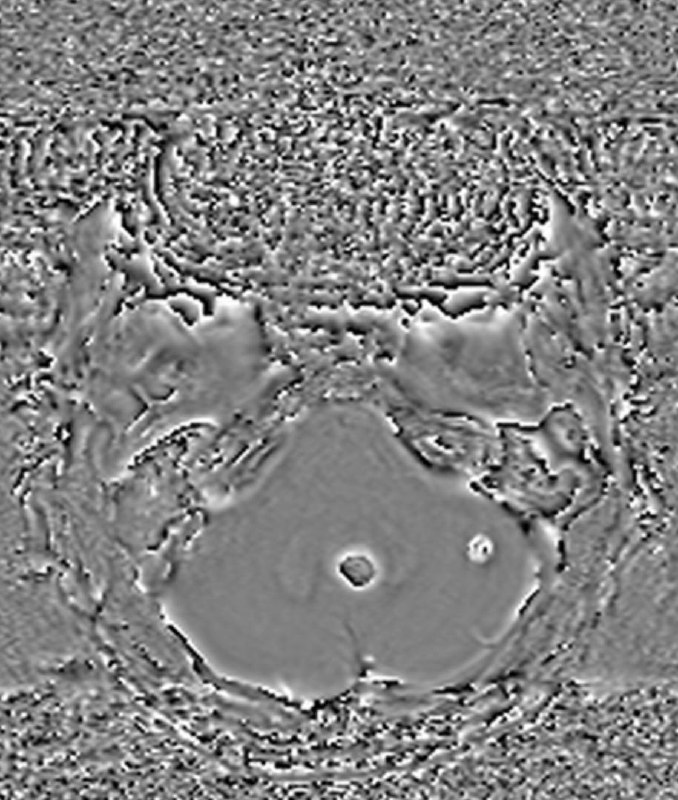

Пациент 35 лет. Жалобы на онемение правой руки. Других жалоб нет.